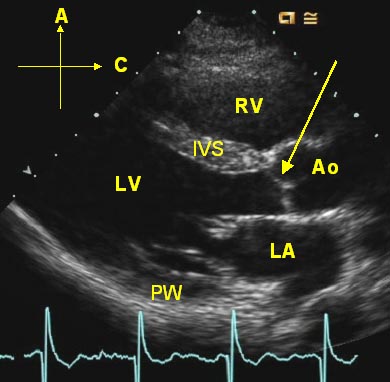

Normal Cardiac Long Axis View

The labeled still image ("Normal Long Axis") is a still frame from an echocardiographic long axis view, a tomographic slice from the left ventricular apex to the base of the heart.   The labels represent:

IVS - interventricular septum

LV - left ventricular cavity

LA - left atrium

RV - right ventricle (a portion of its outflow tract)

PW - posterior wall of the left ventricle

Ao - aortic root

A - Anterior

C - Cephalad

The arrow points to the closed aortic valve plane.  The mitral valve is open (is this in diastole or systole?).